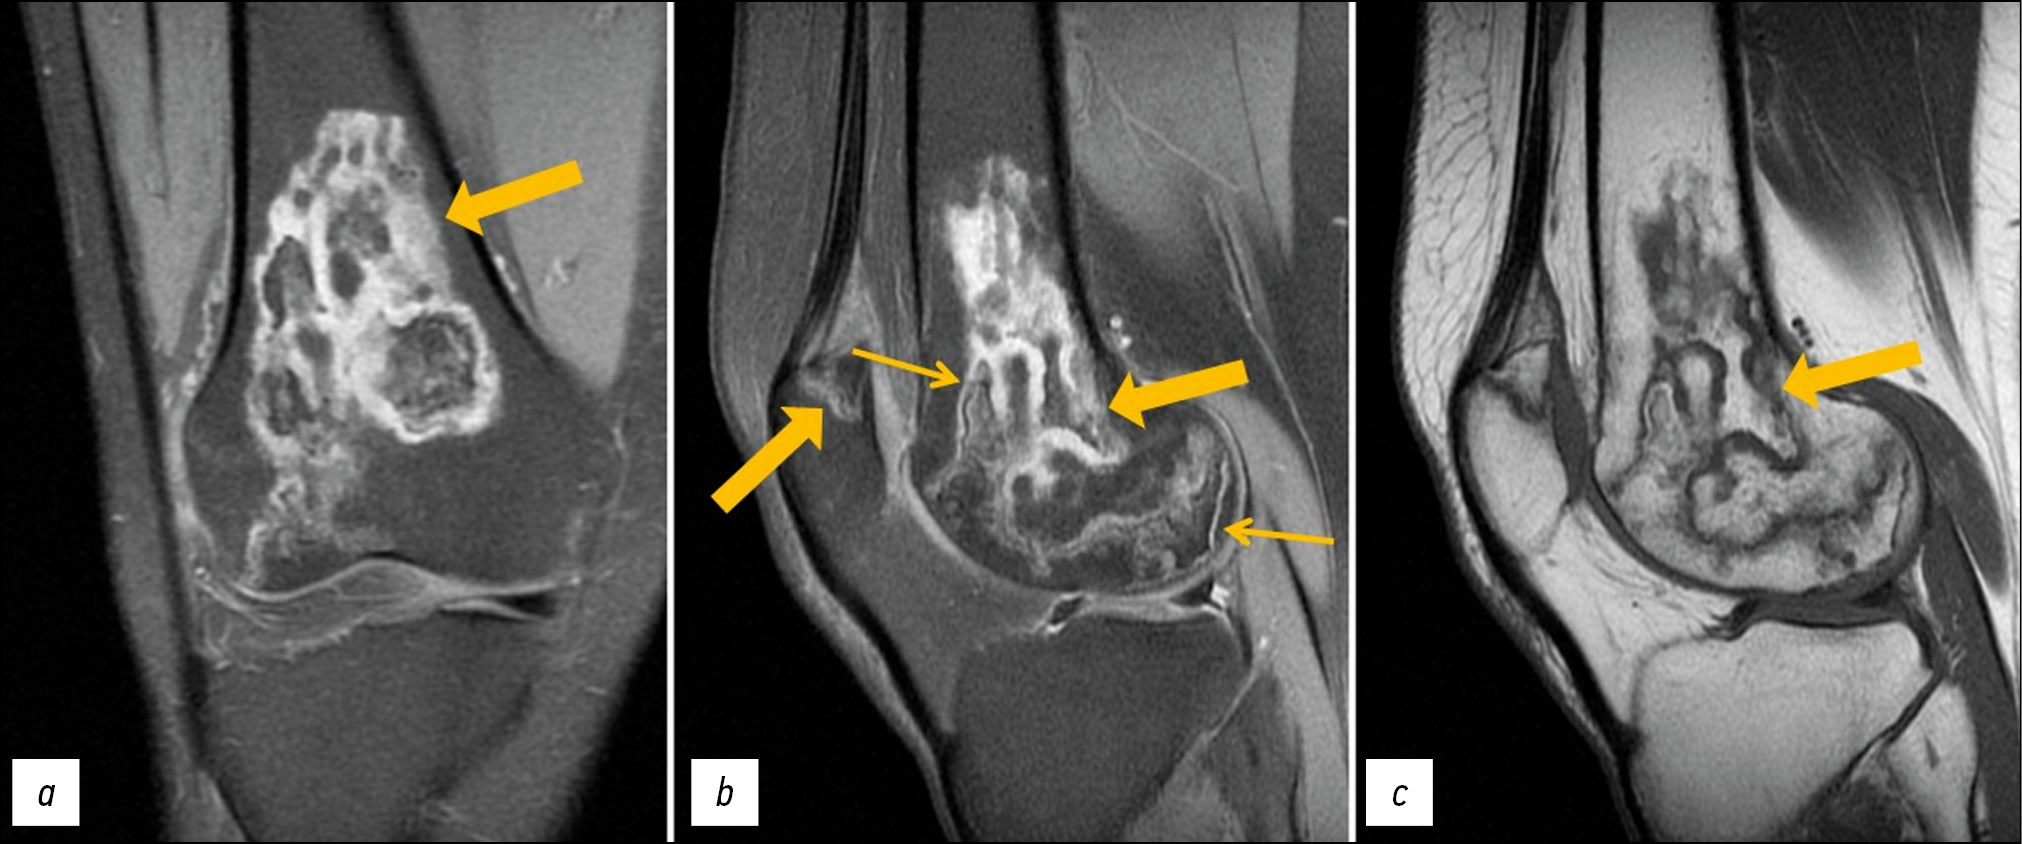

A follow-up MRI of both knee joints revealed positive changes: Previously identified lesions had become substantially less severe (Figs. 3 and 4).

Fig. 4. Follow-up MRI of the right knee joint: PDWI with fat suppression in the coronal (а) and sagittal (b) plane and T1WI in the sagittal plane (с). Thick arrows indicate areas of bone marrow edema in the form of a heterogeneous, irregularly shaped (“geographic”) MRI signal of femoral condyles and patella; thin arrows indicate the “double line” sign in the form of internal hyperintense (granulation tissue) and external hypointense (osteosclerosis) lines on PDWI.